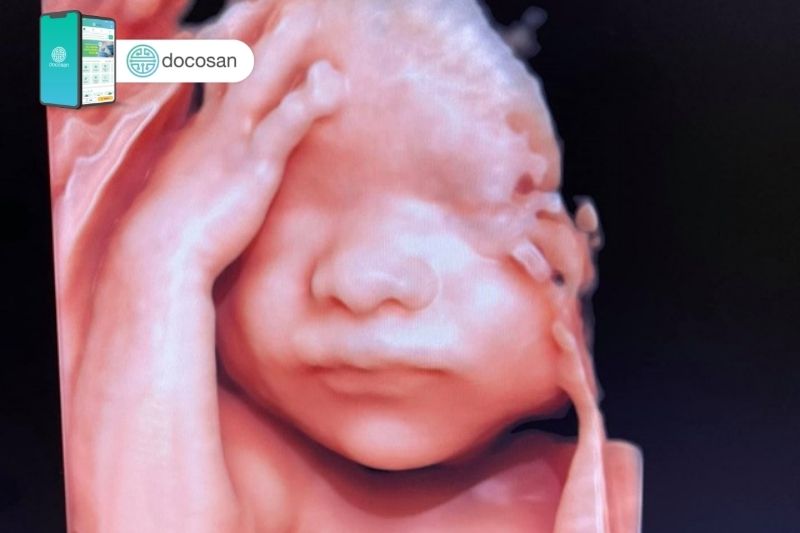

Siêu âm 5D là phương pháp mới nhất hiện nay giúp các mẹ bầu nhìn thấy được hình ảnh thật sinh động của thai nhi trong bụng và giúp bác sĩ chẩn đoán sớm các dị tật bẩm sinh. Vậy các sản phụ cần lưu ý biết những gì về siêu âm 5D, hãy cùng Docosan tìm hiểu nhé!

Siêu âm thai 5D là phương pháp áp dụng sử dụng sóng siêu âm để quan sát chuyển động của thai nhi đang trong tử cung. Phương pháp này sẽ đưa ra hình ảnh giống như bạn đang xem video trực tiếp và giúp các mẹ bầu có thể quan sát một cách rõ nét, chân thực nhất cử chỉ biểu cảm cũng như hình thái của con mình. Đồng thời, siêu âm 5D cung cấp các chỉ số giúp bác sĩ có thể chẩn đoán, phát hiện sớm các dị tật thai nhi ngay từ những tháng đầu tiên của thai kỳ.